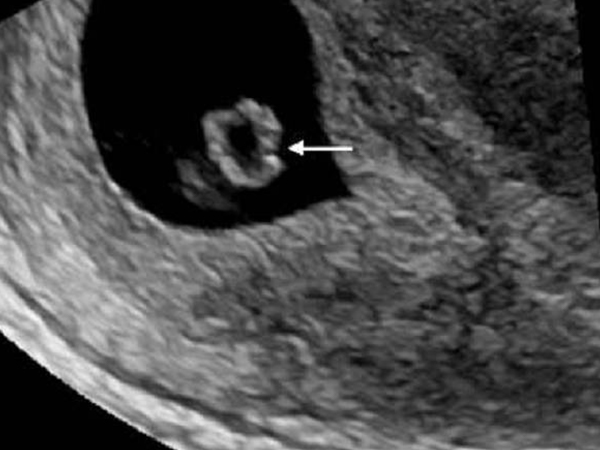

卵黄囊之所以会消失其实是因为其独特的组织功能,卵黄囊的壁是由胚外内胚层和胚外中胚层构成,胚外中胚层在怀孕4到5周便形成许多血岛,是胚胎最早形成血管和血细胞的部位,是胚胎最早的造血场所,同时也有着新陈代谢、免疫和营养的作用。

卵黄囊是胚胎早期的造血场所

但是随着怀孕时间的增加,胎盘会逐渐发育,当胎盘功能发育成熟就会逐渐代替卵黄囊的功能,从而卵黄囊就会逐渐的萎缩,因此直到孕12周后卵黄囊就会慢慢消失。但是如果卵黄囊迟迟不消失的话就需要引起重视。

因为按照正常的发育进度来看,卵黄囊消失是正常现象,但是如果一直不消失的话有可能会持续以往的作用,也有可能不利于胎儿发育,建议持续关注,如果对胎儿没有任何影响,或许会一直伴随到分娩。